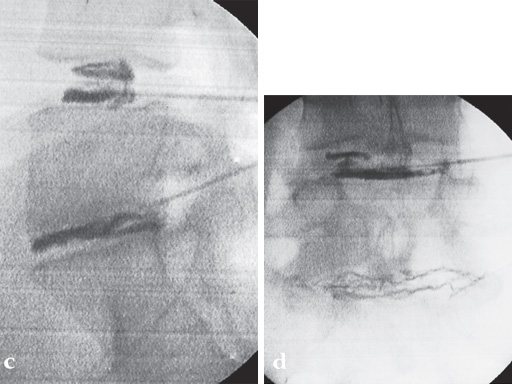

A 37-year-old female (65 kg and 170 cm tall) who suffered from back (L5/S1) and leg pain without neural compression for 2.5 years. She had a full range of conservative treatment and rehabilitation without benefit and reports a significant improvement in symptoms and function following surgery. She has returned to work with minimal restrictions in ongoing activities.

Intraoperative pictures.